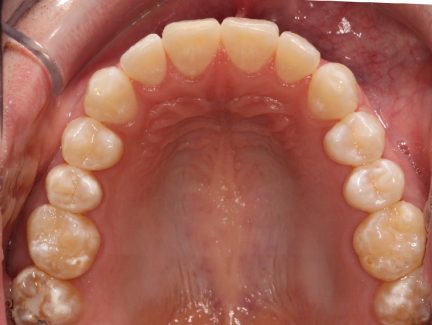

- Des arcades harmoniques ont été réalisées

État initial

État final